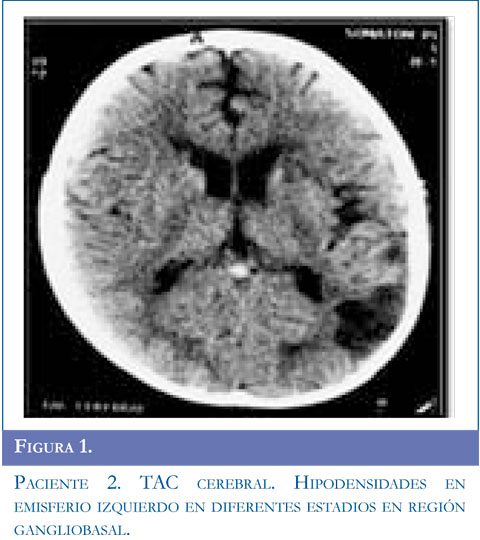

Ingresa al servicio de urgencias por presentar alteración de la marcha dado por disminución de la fuerza en hemicuerpo derecho y dificultad para el habla, acompañado de movimientos clónicos de miembro superior derecho, sin perdida de conciencia la mirada de 10 segundos de duración, se repiten en 5 oportunidades y ceden con benzodiacepinas. Se inició manejo anticonvulsivante. Al examen tenía parálisis facial derecha periférica, hemiparesia derecha con hiperreflexia músculotendinosa, disimetría, disdiadococinesia ipsilateral y afasia motora. Se realizó TAC simple de cráneo y contrastado con lesión gangliobasal izquierda de características isquémicas. Presentó clonias de brazo y aumento de la debilidad faciobraquial derecha, hemianopsia heterónima derecha, se realizó RMC con hipodensidad parieto temporal izquierda compatible con lesión isquémica en territorios de arteria cerebral media izquierda. Se inició enoxaparina1mg/k/dosis y calcio antagonista. El perfil hematológico fue normal. La panangiogra-fía evidenció enfermedad de Moyamoya estadio V de Suzuki. Valorado por neurocirugía se consideró manejo quirúrgico y el día 19 del cuadro clínico se realizó encefaloduroarteriosinangiosis. En la actualidad tiene afasia motora en mejoría, hemiparesia derecha y componente distónico ipsilateral, hiperre-flexia derecha, continúa manejo con fisiatría, terapia física, ocupacional y del lenguaje. Figuras 1,2 y 3.

Para el estudio de esta enfermedad ante la sospecha clínica se deben solicitar estudios radiológicos como tomografía computarizada de cráneo (TAC) evidenciando áreas pequeñas de hipodensidad que sugieren hemorragia o isquemia en región cortical, ganglio basal, profundidad de sustancia blanca o región periventricular; sin embargo, la TAC puede ser normal si el paciente presenta un evento isquémico transitorio. En todos los pacientes de esta serie, se solicitó TAC encontrandose lesión focal secundaria al evento vascular en regiones subcorticales y gangliobasales. La disponibilidad de RM y angiografía por RM se ha convertido en el método diagnóstico del síndrome de Moyamoya. Un infarto cerebral agudo es más probable que se detecte con el uso de imagen por difusión, un infarto cerebral crónico se observa en RM en T1-T2. El flujo sanguíneo cortical disminuido se observa en la secuencia FLAIR como una señal lineal intensa que sigue la forma de los surcos llamado "signo de la hiedra" (14). Los hallazgos más frecuentes en RM son reducción del flujo de la arteria carótida interna, arteria cerebral anterior y media hasta llegar a ausencia de flujo sanguíneo en ganglios basales y tálamo con formación de vasos colaterales; en este informe el examen confirmatorio se realizó con angiografía, se debe realizar estudio de 5 o 6 vasos que incluyan arterias carótidas externas, carótidas internas y 1 ó 2 arterias vertebrales según colaterales que se presenten. El diagnóstico definitivo se basa en el aspecto arteriográfico caracterizado por estenosis de la arteria carótida interna a nivel distal, extendiéndose a la región proximal y media (15). La severidad de la enfermedad se clasifica de I a VI estadios de progresión según el sistema de clasificación de Suzuky (16) (Tabla 1). En los casos presentados el grado de estatificación fue IV y V mientras que en la serie de González (5) existieron varias presentaciones I, III y VI; Galicchio (6) presentó casos en estadio II a III.